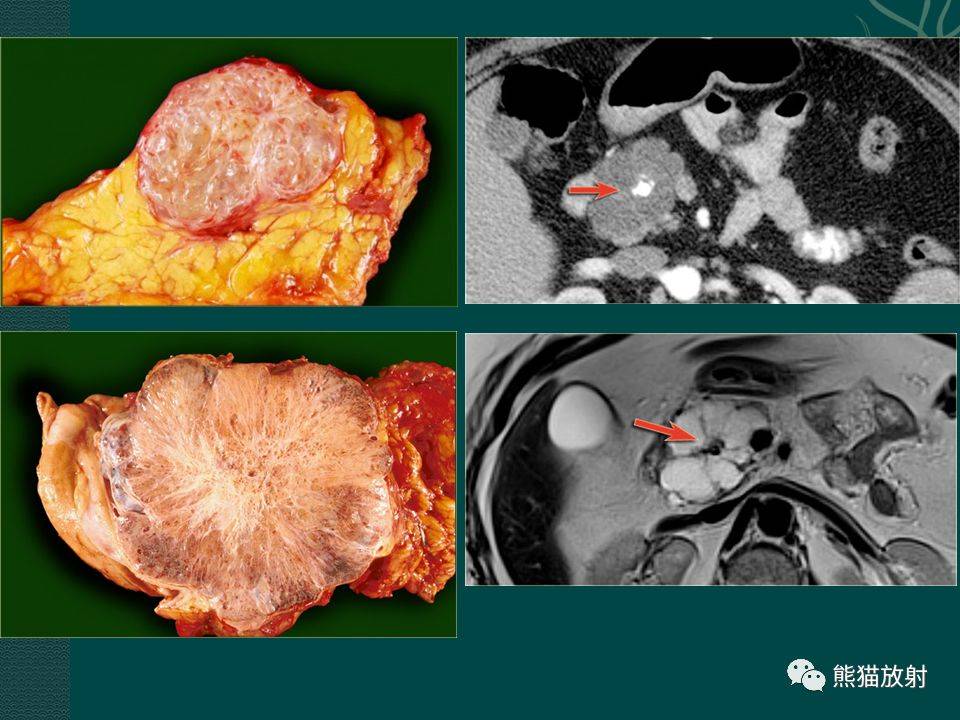

胰腺及脾脏病变影像诊断

脾血管瘤